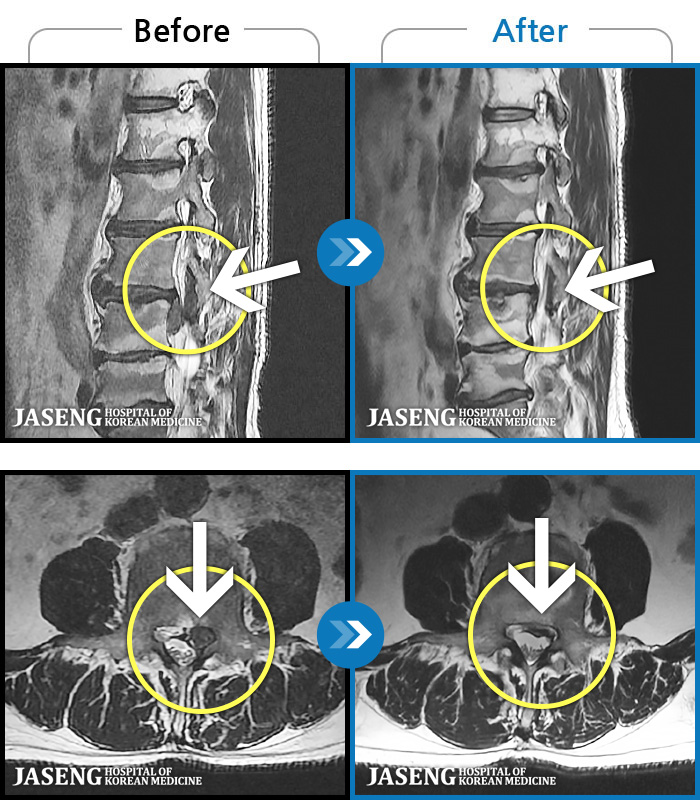

MRI ġ

1,237 MRI ũ ʸ Ȯϼ.

[Ȼ_㸮ũ] 㸮 ְ ٸ ȱⰡ .

No.1237

ȸ 2,760

2025.10.02